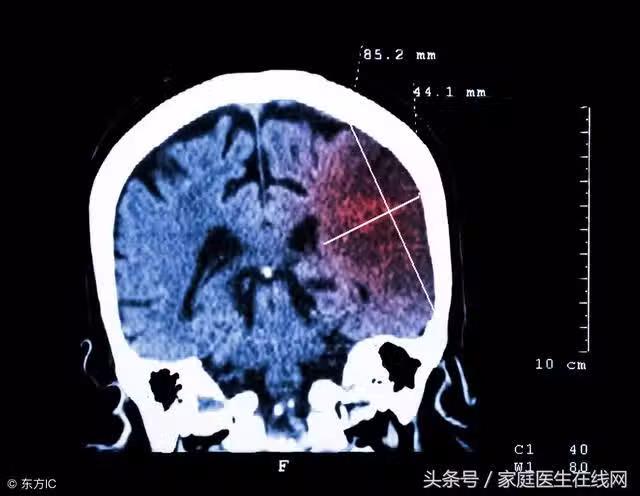

這5件事會導致腦梗反覆發作